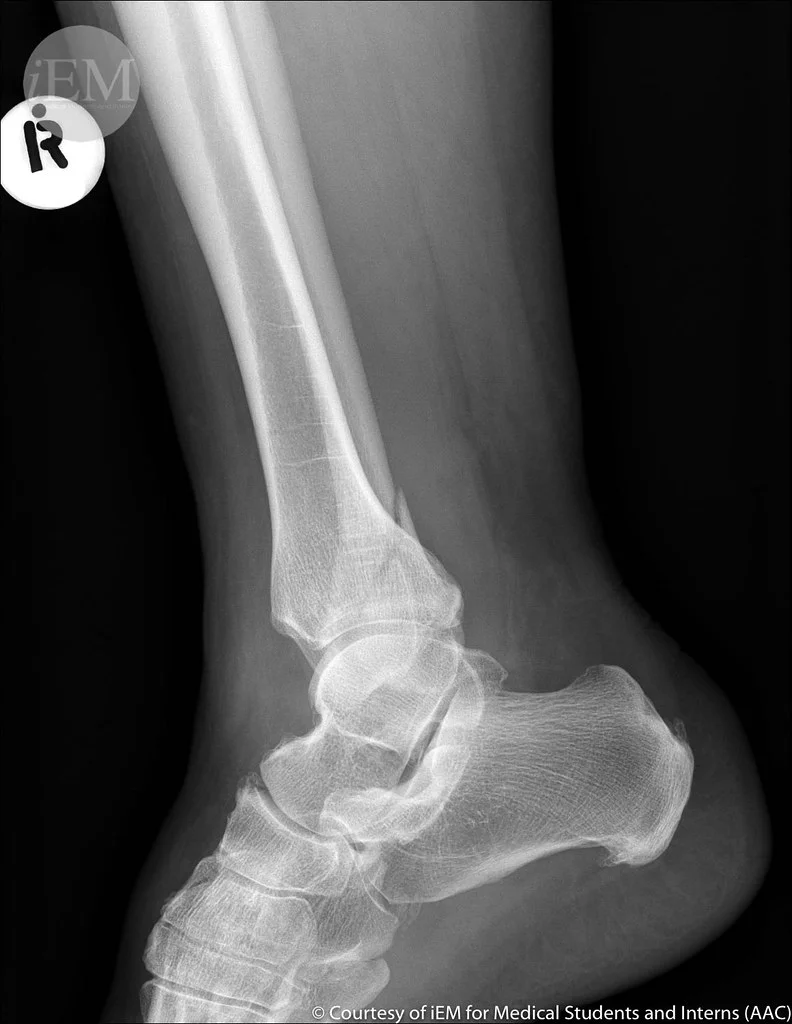

Diagnosis and Imaging Techniques

Diagnosing a fibula stress fracture involves a combination of clinical examination and imaging tests. Here’s what to expect:

- Physical Examination: Your doctor will assess for tenderness, swelling, and pain in the lower leg.

- Imaging Tests:

- X-rays may initially miss minor fractures.

- MRI or CT scans provide detailed images, confirming the extent of the fracture.